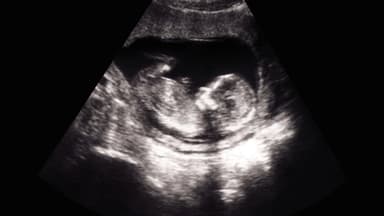

Trong hành trình mang thai, việc nhận được kết quả siêu âm có dấu hiệu bất thường luôn khiến các mẹ bầu không khỏi lo lắng và hoang mang. Một trong những chẩn đoán đáng chú ý thường gặp ở 3 tháng đầu thai kỳ là tình trạng giãn bàng quang ở thai nhi. Nghe qua có vẻ đáng sợ, nhưng trên thực tế, không phải mọi trường hợp đều mang tiên lượng xấu hay đe dọa trực tiếp đến thai kỳ. Vậy tình trạng này thực chất do đâu mà có, mức độ nguy hiểm ra sao và mẹ bầu cần xử trí như thế nào để đảm bảo an toàn cho bé yêu?

Tình trạng giãn bàng quang ở thai nhi (hay còn gọi là bàng quang to – Megacystis) được xác định khi đường kính dọc bàng quang (LBD) đo được từ 7mm trở lên thông qua siêu âm thai ở quý 1 (khoảng từ tuần thứ 10 đến 14). Tình trạng này có tỷ lệ bắt gặp khoảng 1/1500 đến 1/1831 thai kỳ, trong đó bé trai có nguy cơ mắc bệnh cao gấp 8 lần bé gái.